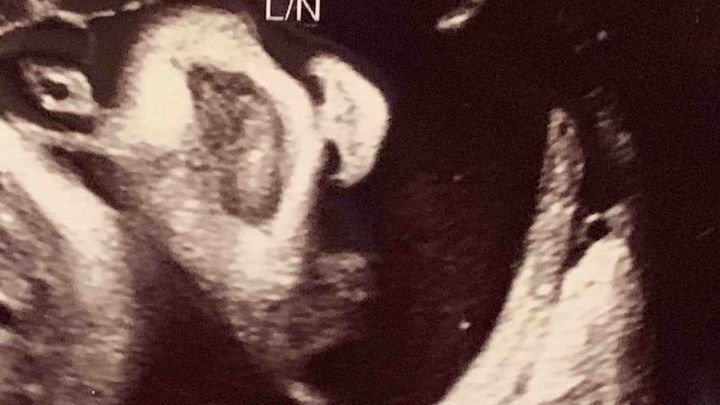

My name is Daina, and I am a sonographer and mother of two. It has been a dream of mine to support expecting mothers with their pregnancy journey, in experiencing their baby in 3D.

I was first interested in Ultrasound when I went to my first appointment. I was so eager to see who I created! So much joy filled my heart. I remember asking the technician so many questions, that I knew she was probably tired of me, but at that moment I fell in love with the skill and the art. I knew I wanted to start a career in sonography. I wanted to make people feel as happy as I did, knowing how amazing our bodies could be. Years passed and fast forward to now: I have followed my dreams and have gotten my healthcare degree along with my ultrasound degree, all while being pregnant with my second child! Before I entered the Diagnostic Medical Sonography program, I was interviewed by the program director, and I had to come up with a five-year plan. In my five-year plan, I talked about gaining the experience and helping others through diagnostic ultrasound, but, ultimately opening up my own Ultrasound studio - bringing joy to the families like I had experienced during my pregnancies. I’ve had some experience in the hospital setting, which I absolutely loved, but as I approach my fifth year I am ready to expand my services

2D black and white ultrasound photos

3D/4D ultrasound photos and videos